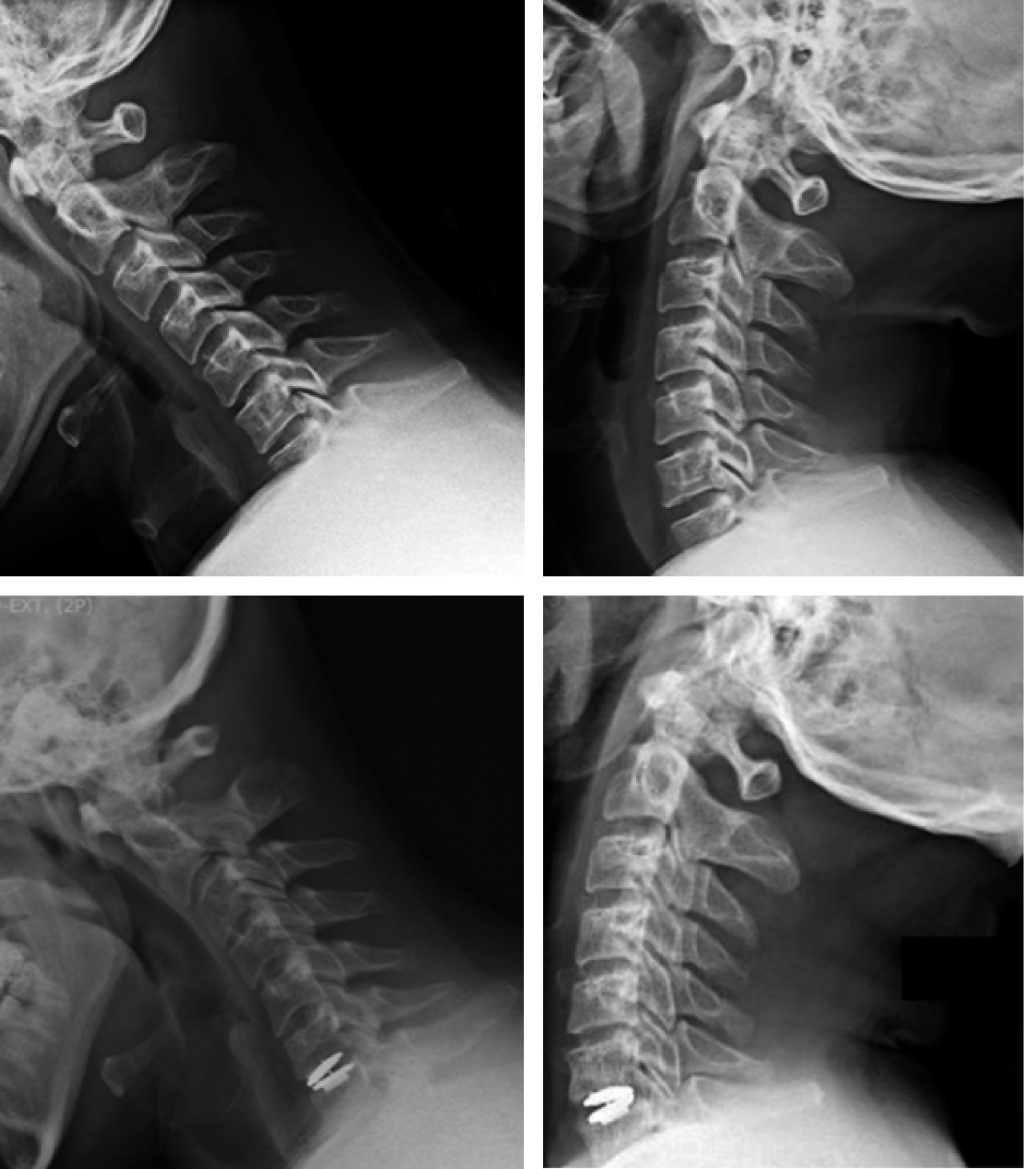

Figure 2